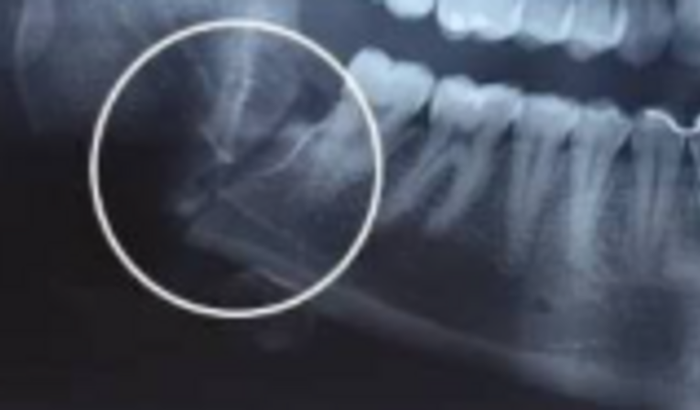

Olá, sou o Diego e trabalhava como motoboy, sofri um acidente, fraturei meu braço e o maxilar em dois lugares, preciso de cirugia urgente, não aguento mais as dores e não conseguir me alimentar, a cirugia custa 60 mil, não tenho de onde tirar, e não sei a quem recorrer mais, o SUS negou minha cirugia, desde o acidente já perdi 16kg por não conseguir me alimentar direito, meu braço ficou travado e sem espectativa de voltar a funcionar, já faz quase 8 meses que estou nesse sofrimento, recorri até o óptimo momento tentar pelo SUS, mas agora tenho a resposta convicta que não vou conseguir, e meu último recurso é esse!